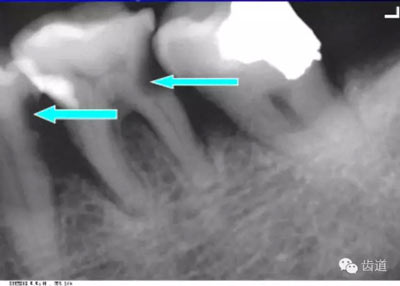

牙頸部Burnout征象:有時因投照技術(shù)問題而造成牙頸部近中或遠(yuǎn)中呈低密度影像,位于牙釉質(zhì)和牙槽嵴頂之間。